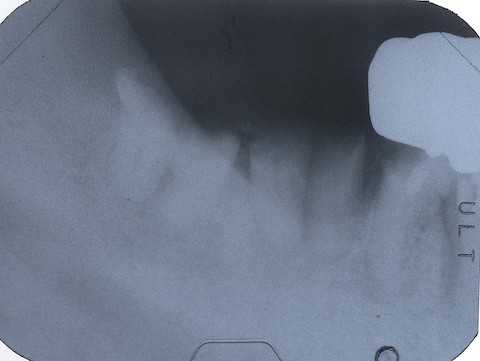

今日も野戦病院シリーズ26(CK破折) 2025.10.25